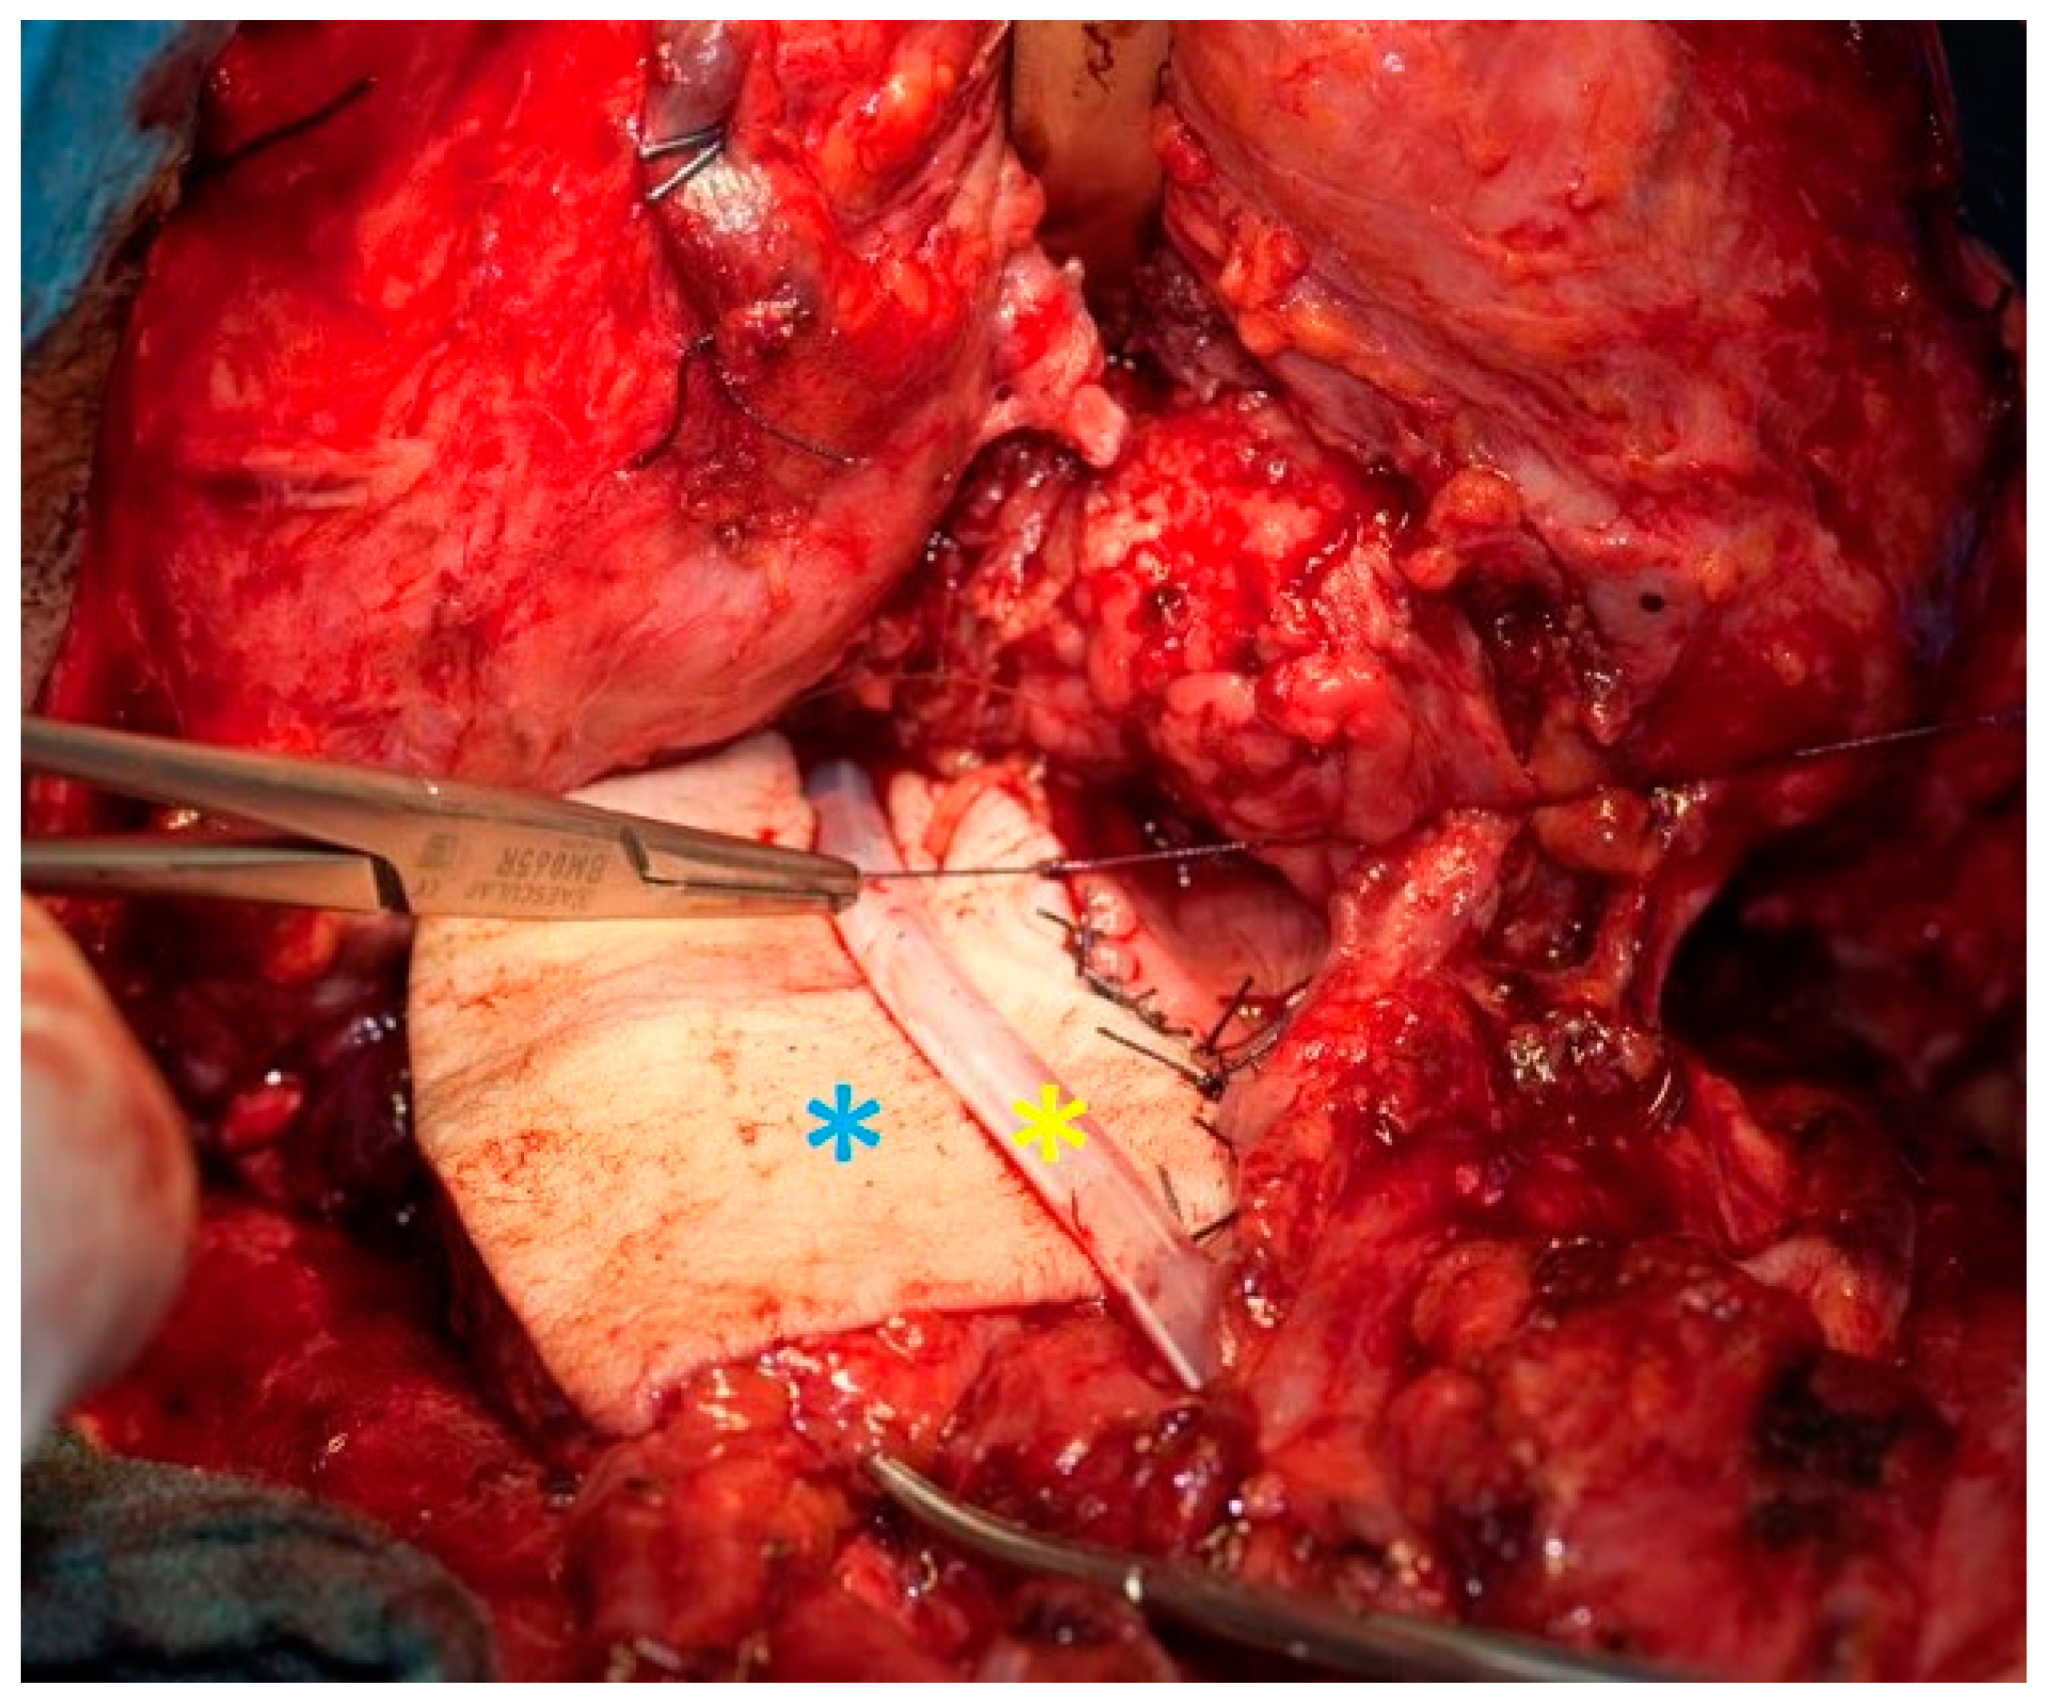

2.2. Surgical Technique for Total Laryngectomy